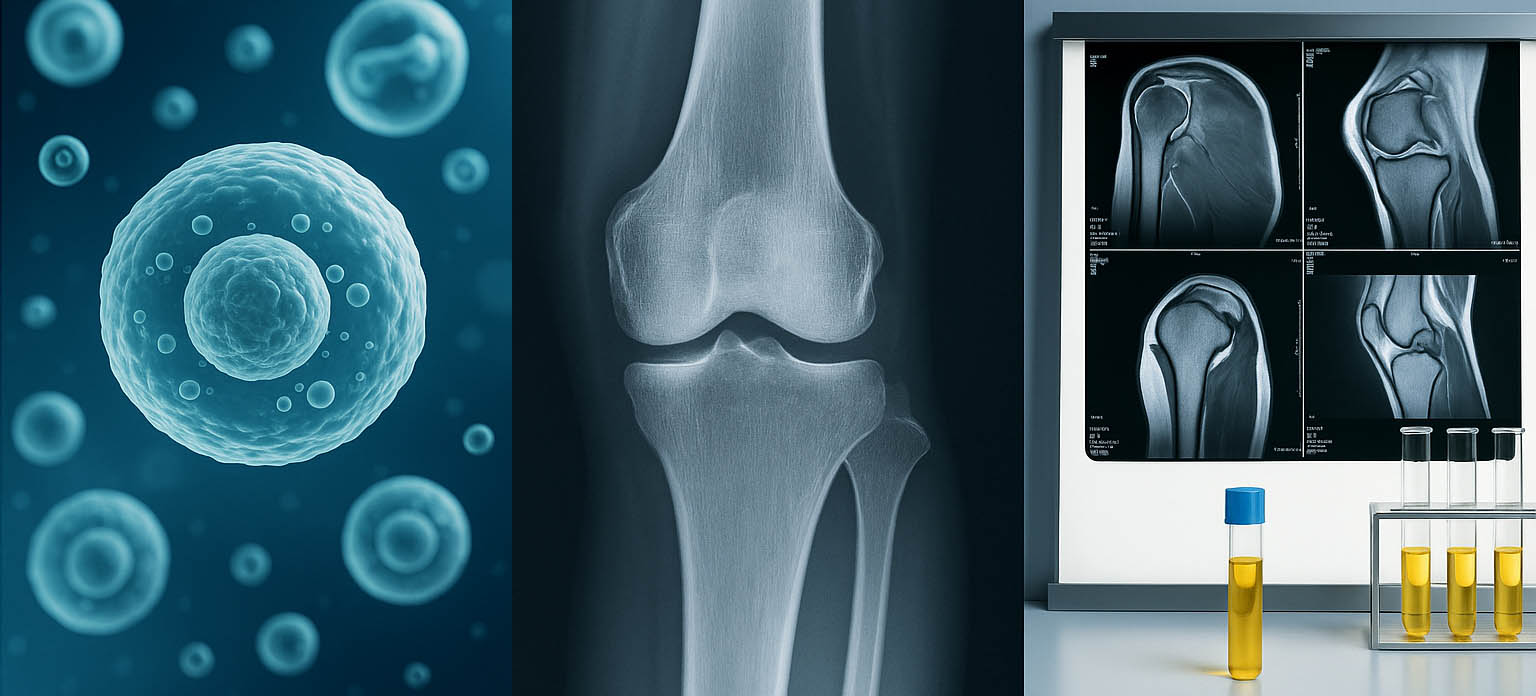

I'll never forget the conference in New York City where I first witnessed what biological medicine could really do. A colleague showed me imaging from a patient with a partial rotator cuff tear—the kind I'd normally send straight to surgery. Six months after treatment with concentrated biologics from the patient's own body, the follow-up MRI showed something I'd been told was impossible: actual tissue healing. Not just pain relief. Real, structural healing.

I spent the next two years diving deep into the science, training with pioneers in the field, and honestly, unlearning a lot of what I thought I knew. At Unicorn Bioscience, we've built something special. We're using your body's own healing mechanisms—concentrated and targeted—to actually repair damage, not just mask it.

But your body isn't a machine. It's incredibly intelligent, constantly trying to heal itself. What we do at Unicorn Bioscience is simple in concept but revolutionary in practice: we take your body's own healing factors, concentrate them dramatically, and put them exactly where they're needed. No foreign substances. No synthetic materials. Just your biology, amplified.